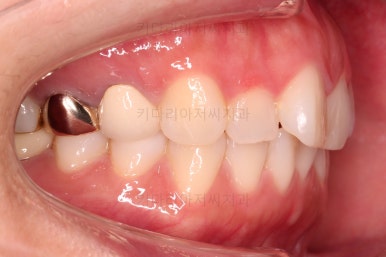

그리고 아랫니 송고니 옆 잇몸에 보시면 미니스크류가 식립이 되어있는데요.

이는 솟구친 아래 앞니의 높이를 조절하기 위해 사용이 됩니다.

이부분이 해결이 되어야 좀 더 완성도 높은 부분교정이 가능해요.